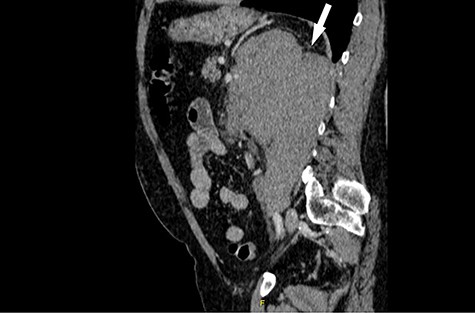

His CT scan identified large left renal tumour invading psoas muscle. Left mid ureteric tumour as well. Multiple regional nodes. No hepatic, pulmonary or osseous metastasis. The scan was highly suggestive of metastatic transitional cell carcinoma (Figs. 1 and 2).

Computed tomography (CT) sagittal section showing predominant bulk of the mass is extrarenal that posteriorly breaches the fascia to involve the diaphragm and psoas muscle. Medially it reaches the intervertebral foramen.